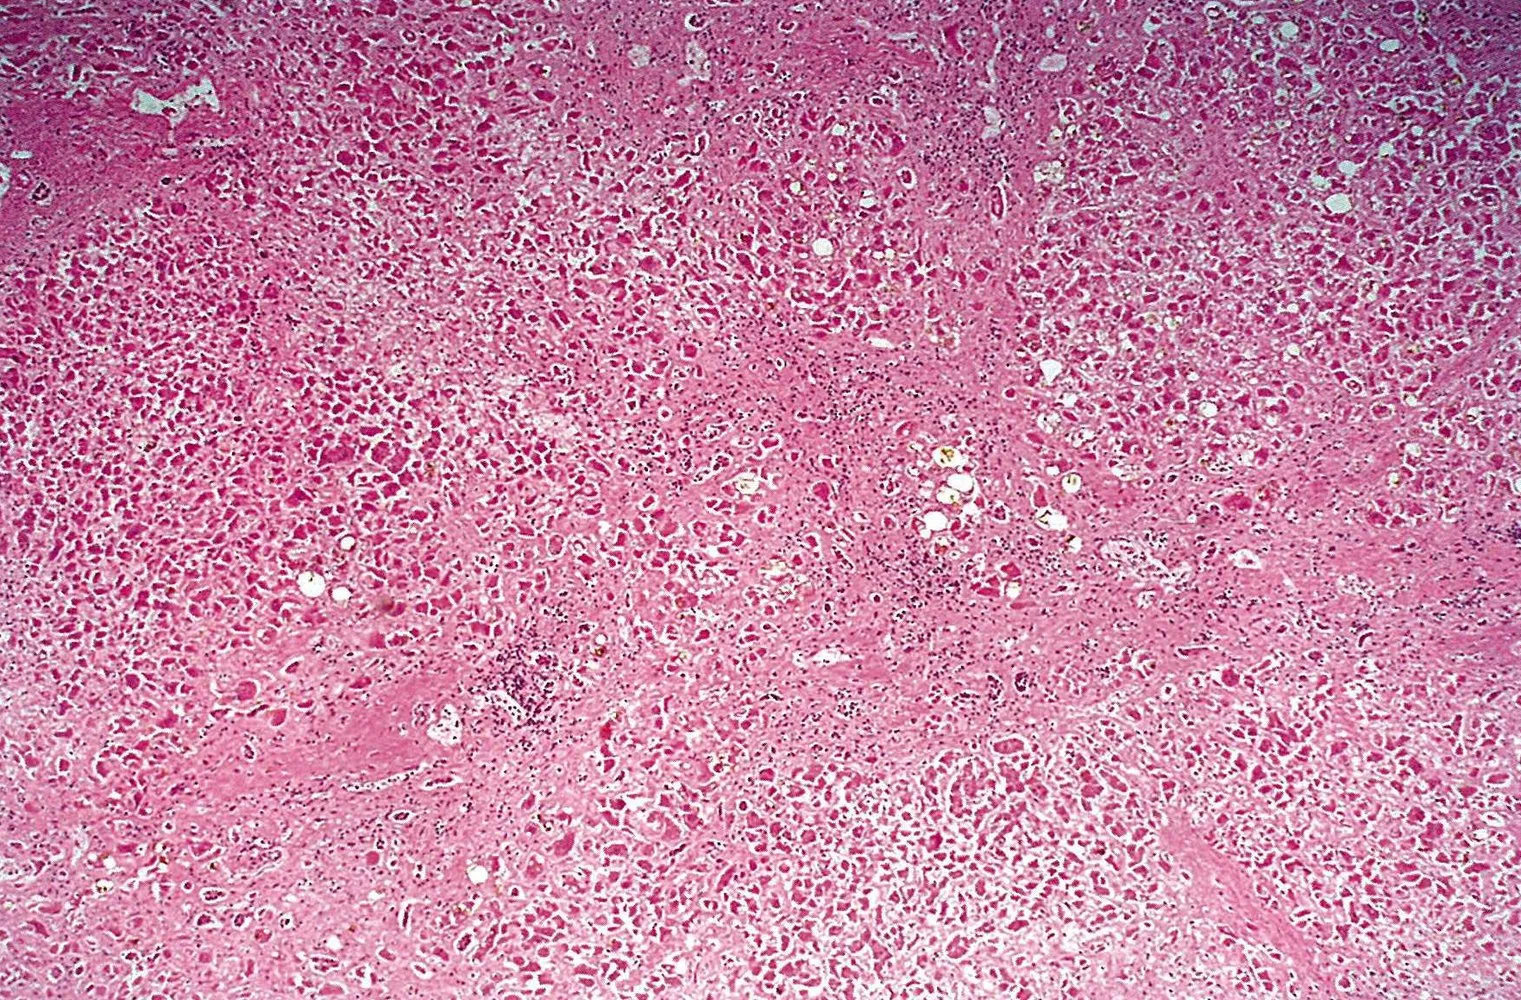

- Mottenfraßnekrose: Periportale Leberzellnekrose mit lymphozytärer Infiltration , spricht für eine chronisch aktive Hepatitisform und ist ein prognostisch ungünstiges Zeichen

Hier: Leberzirrhose bei chronischer Hepatitis B

Mikroskopische Aufnahme der Leber bei chronischer Hepatitis B Infektion (H.E.-Färbung, ca. 50-fache Vergrößerung):

Zu sehen ist ein vollständiger Verlust der histologischen Leberarchitektur (Fehlen definierter Leberläppchen) kombiniert mit breiten, vernetzten Fibrosebändern (gelb markiert).

Diese Befunde weisen auf eine Leberzirrhose infolge einer chronischen Virushepatitis hin.

Quelle: © IMPP